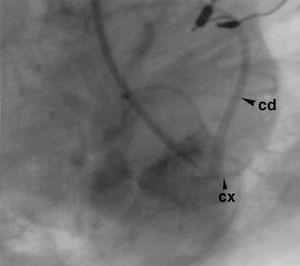

Figura 2. Aortografía. La coronaria derecha nace del seno postero derecho y de ella nace la arteria circunfleja. Cx: coronaria circunfleja (cabeza de flecha pequeña); cd: coronaria derecha (cabeza de flecha grande).

Paciente remitido a los 3 meses de edad por cianosis generalizada (saturación del 78 %), soplo sistólico eyectivo en segundo espacio intercostal izquierdo e hipertrofia ventricular derecha eléctrica. Radiografía de tórax: corazón en zueco, arco aórtico izquierdo e hipovascularización pulmonar. Ecocardiografía Doppler: acabalgamiento aórtico al 50 %, comunicación interventricular subaórtica, estenosis infundibular; válvula pulmonar estenótica con tronco hipoplásico. Gradiente ventrículo derecho-arteria pulmonar 85 mmHg. Resonancia magnética: tronco pulmonar, 4-5 mm; aorta ascendente, 12 mm; rama pulmonar derecha 3 mm; no se visualizó la rama pulmonar izquierda. Se realizó una fístula central aorta-pulmonar a los 4 meses con buena evolución. A los 11 meses cateterismo: presión ventrículo derecho 96/0-7 mmHg; ventrículo izquierdo 86/0-5 mmHg; arteria aorta, 78/33-55 mmHg. No se consiguió pasar al tronco pulmonar. Saturación de la aurícula derecha, 79 %; ventrículo derecho, 78 %; ventrículo izquierdo, 98 %; arteria aorta, 90 %. Ventriculografía derecha: ventrículo derecho hipertrófico con estenosis infundibular y anillo pulmonar estenótico. Rama derecha visible 5 mmHg, rama izquierda ausente (fig. 1). Ventriculografía izquierda: defecto subaórtico, acabalgamiento de la aorta y arco aórtico izquierdo. Aortografía: la arteria circunfleja nace de la corona derecha (fig. 2). Desde el arco aórtico nace una colateral que riega el pulmón izquierdo. Fístula central permeable. Cirugía a los 16 meses: incisión longitudinal de la arteria pulmonar y el anillo, resección parietal del infundíbulo, ampliando con parche transvalvular de pericardio bovino y cierre de la comunicación con parche de Dacron con sutura 6/0. Se anastomizó el tronco pulmonar con la colateral por medio de un tubo de Goretex. Ligadura de la fístula central. Tiempo de isquemia 55 min. Ultrafiltración 500 ml. Durante el postoperatorio el paciente presentó una taquicardia ectópica de la unión con buena respuesta a la aminodarona e hipotermia. Al alta en el estudio ecocardiográfico se observó el defecto interventricular cerrado el tracto de salida derecha con buen calibre y una disminución del gradiente entre ventrículo derecho y la arteria pulmonar (25 mmHg) con flujo en la arteria pulmonar izquierda. A los 10 meses el paciente se encontraba asintomático, gammagrafía pulmonar de perfusión pulmón derecho, 90 %; pulmón izquierdo hipoperfundido, 10 % (normal, 38-45).